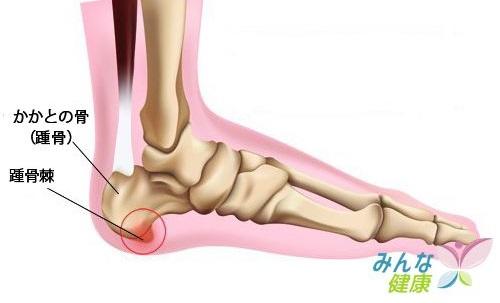

足裏には、土踏まず部分のアーチを構成している足底腱膜という筋肉があり、

足底腱膜は踵から5本の指についております。

ランニングによる持続的な負荷で、足底腱膜部に負担が係り、

足底腱膜自体に炎症が起こる「足底腱膜炎」

踵骨(かかと)の足底腱膜付着部で付着部が引張られ、徐々に骨が膨隆し、

骨棘(こつきょく)という骨の棘(とげ)を作り、

そこに刺激が入ることで、痛みを出すというのパターンがあります。